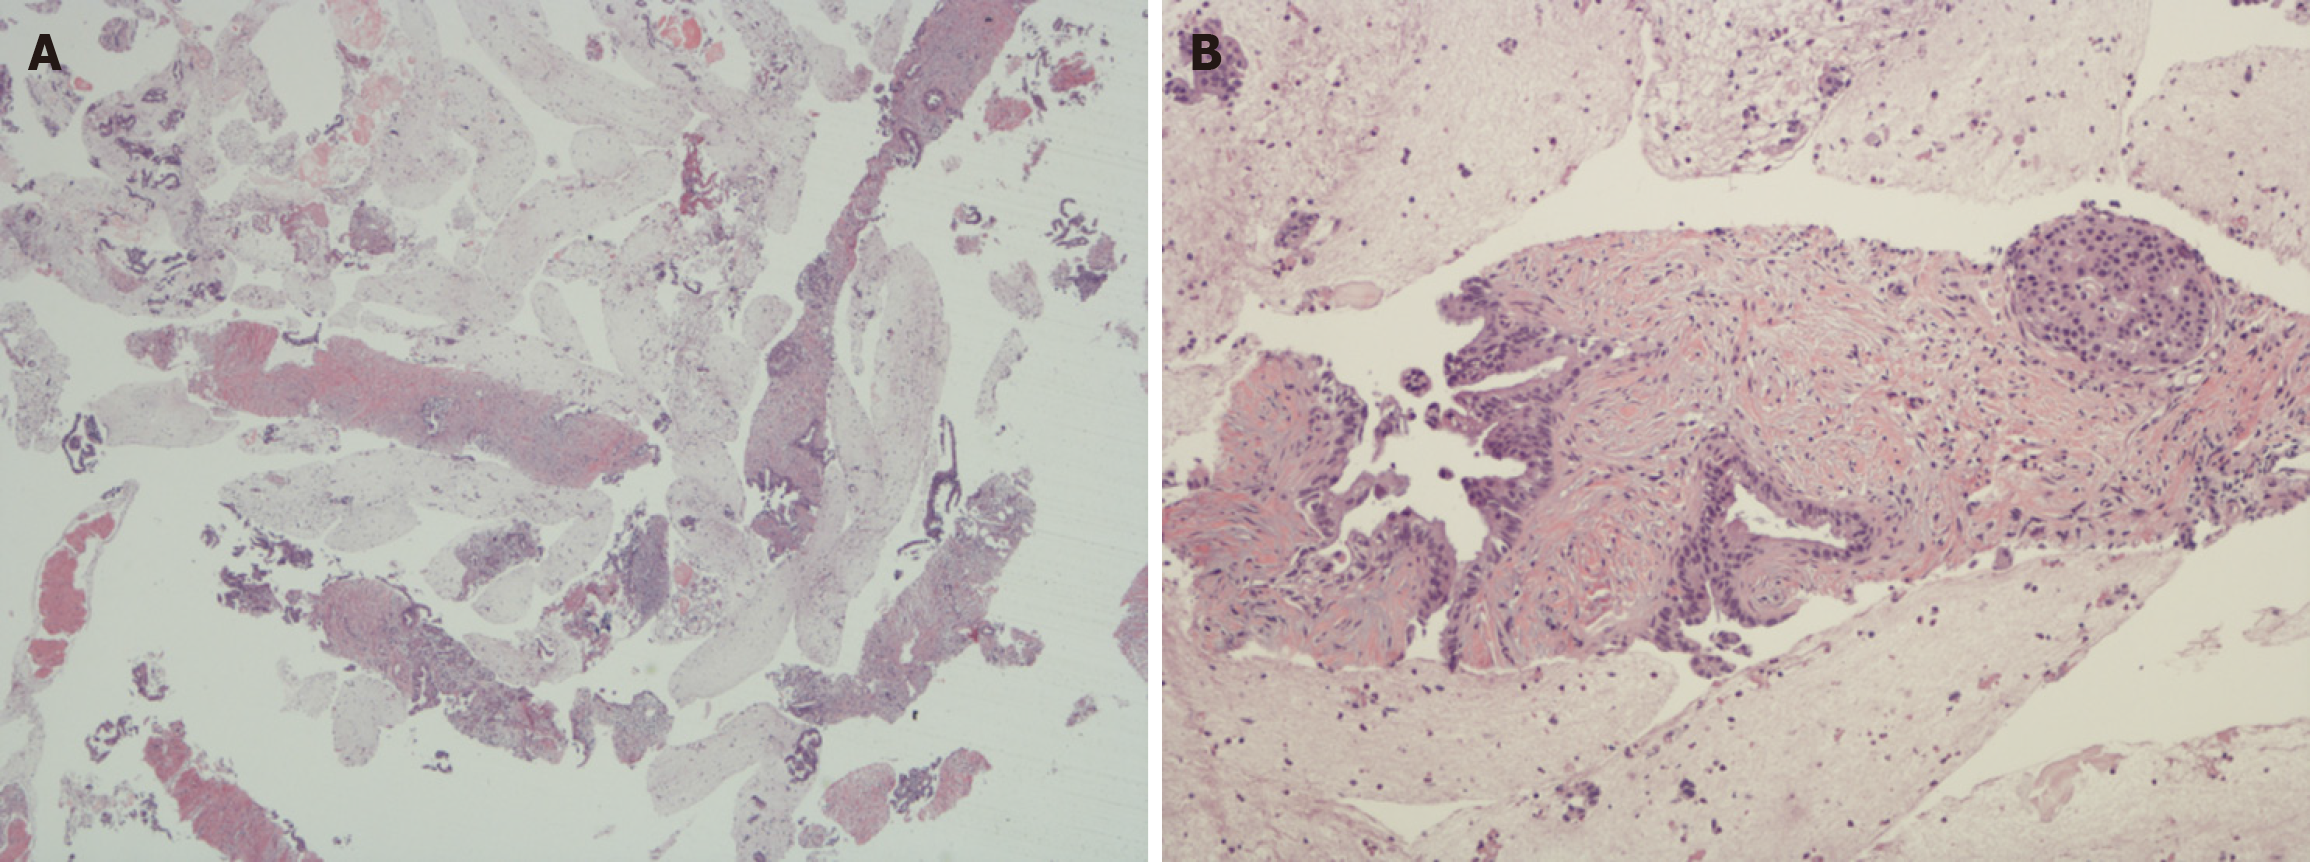

Figure 2 Photomicrographs of poorly-differentiated pancreatic ductal adenocarcinoma.

A: Section from a pancreaticoduodenectomy specimen showing poorly differentiated pancreatic ductal adenocarcinoma of the pancreatic head. There are poorly formed infiltrative glands in a desmoplastic stroma (original magnification × 100); B: Ki67 immunohistochemistry slide from same case. The positive tumor cell nuclei are brown whereas the negative are blue. The Ki67 Labelling index in this field is 9.4%. Most studies for pancreatic ductal adenocarcinoma use the average count, but for pancreatic neuroendocrine neoplasms, the guidelines mandate selecting the hotspots.